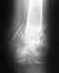

Очень нужен совет,Девушка 27 лет, 19 февраля 2016 года получила перелом н\лодыжки со смещением и надрывом дельтовидной связки.

Сделали репозицию, загипсовали. 30 марта сделали рентген и сняли гипс, не смотря на то что в заключении врача рентгенолога было написано "костной мозоли не выявлено". Врач сказал давать потихоньку нагрузку и назначил физиопроцедуры (лфк и лазер). 20 апреля пришла на прием и попросила проверить ногу еще раз, т.к. поднималась температура и очень болела нога. Отправили на СКТ(снимки прилагаю) Врач посмотрев их сказал что ждем 12 мая еще раз придешь на прием посмотрим, прописал таблетки Осталон и опять физиопроцедуры (грязи и электрофорез с кальце-хлором).